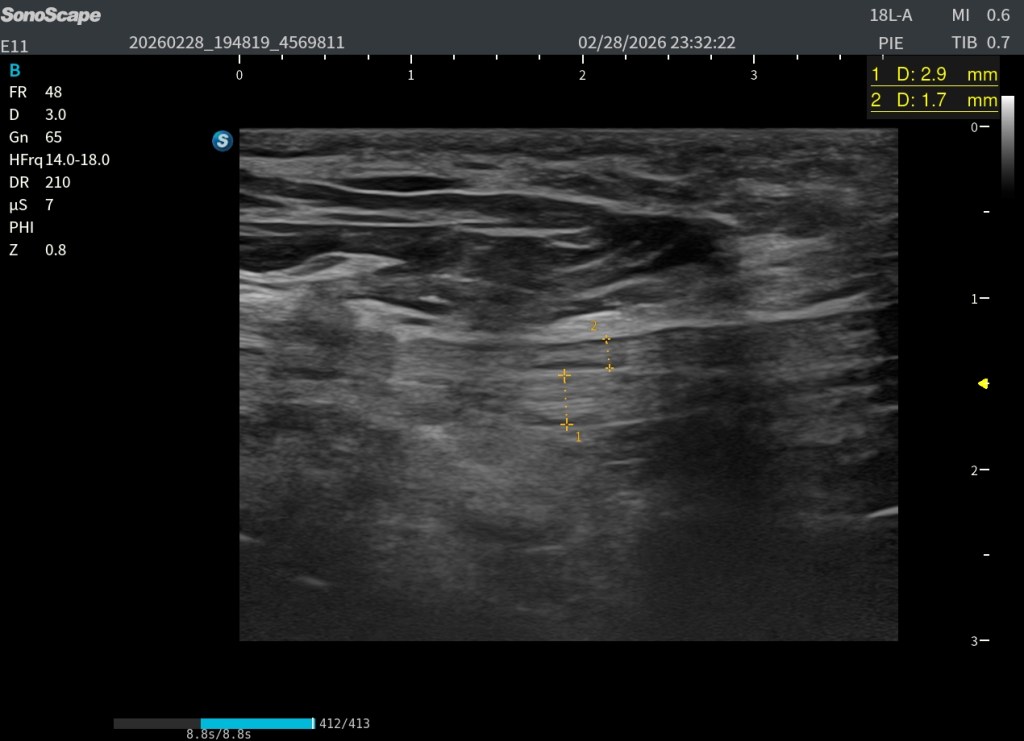

En la imagen superior (en corte axial) a este texto observas dos medidas claramente señaladas. La número uno corresponde al flexor largo del primer dedo (FHL) y la número dos corresponde al flexor largo de los dedos (FDL). Puede apreciarse cómo la estructura marcada con el número dos pasa por encima de la número uno, confirmando que el FDL se sitúa superficial al FHL en el punto de cruce. Además, se observa que el tendón número dos presenta una disposición fibrilar distinta, lo que explica que se visualice ligeramente más hipoecogénico debido a un discreto efecto de anisotropía.

La estructura marcada con el número 2, correspondiente al flexor largo de los dedos (FDL), además de ser de menor calibre, aparece ligeramente anisotrópica. Esto se debe a que la insonación está optimizada para visualizar con máxima nitidez el patrón tendinoso del flexor largo del primer dedo (FHL), señalado con el número 1. Esa adaptación del ángulo permite definir con claridad la ecoestructura fibrilar del FHL, aunque penalice parcialmente la visualización del FDL.